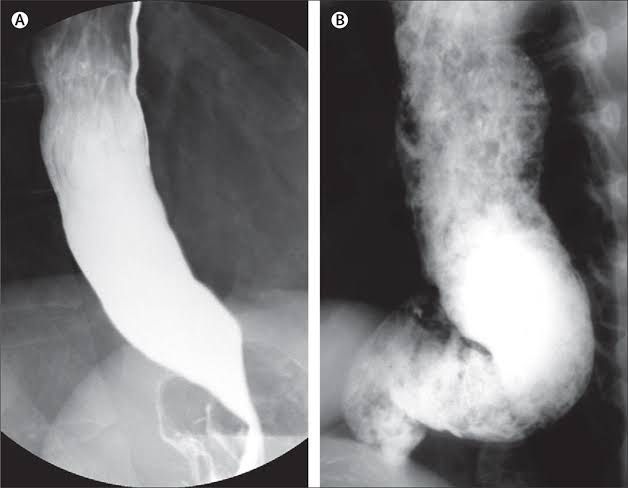

Why your esophageal muscles fail to contract and relax normally is unknown. One theory is that achalasia is an autoimmune disease (your body attacks itself) that is triggered by a virus. Your immune system attacks the nerve cells in the muscle layers of the walls of your esophagus and at the LES. Your nerve cells, which control muscle function, slowly degenerate for reasons that are not currently understood. This results in excessive contractions in the LES. If you have achalasia, the LES fails to relax and food and liquids can’t pass through your esophagus into your stomach. A rare form of achalasia may be inherited. More research is needed.